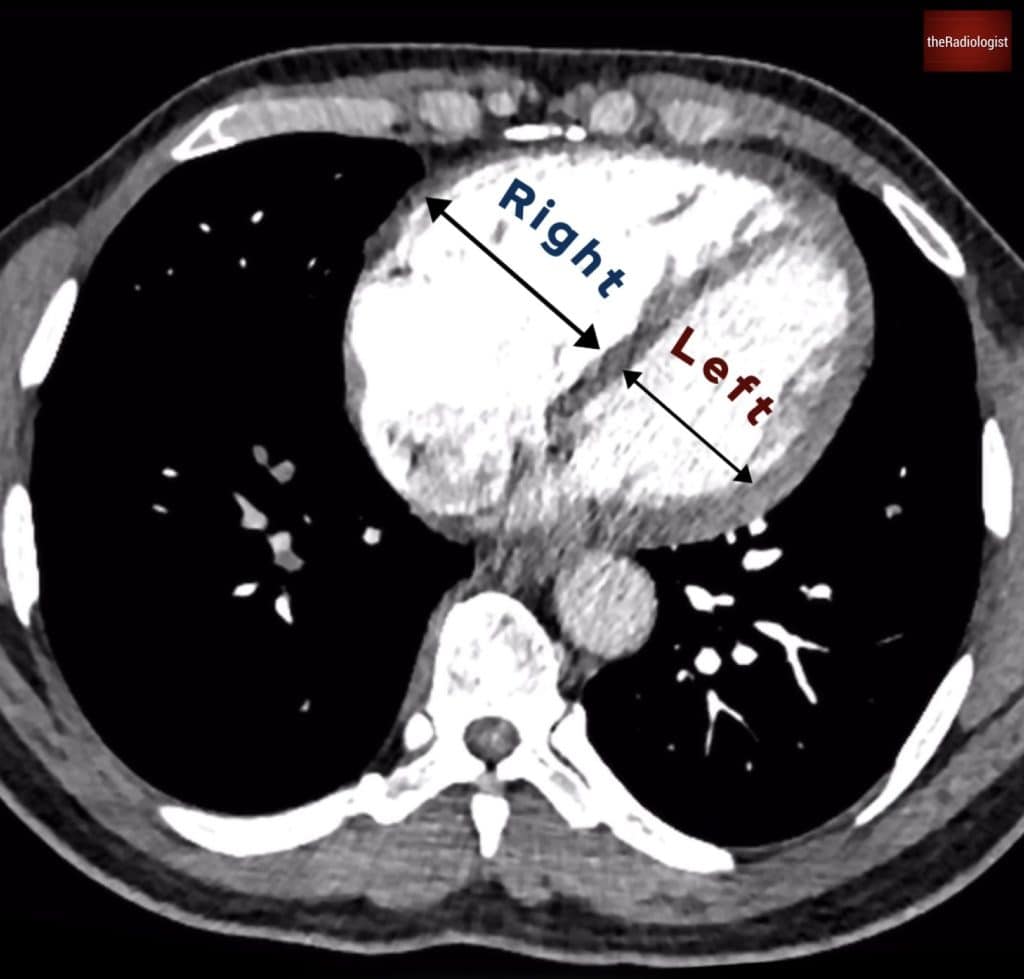

1. Right heart strain

One of the most important aspects of reviewing a CTPA is identifying signs of right heart strain. The RV/LV diameter ratio is key: an RV larger than the LV suggests raised right-sided pressures. To measure this:

• Measure the inner borders of the ventricles (endocardium)

• Does not have to be on the same slice

• Measure in the basal third closest to the valve

This is the key finding and what correlates better with Echo findings and morbity/mortality than signs like septal bowing or reflux of contrast which I like to consider signs that can support a diagnosis of right heart strain on CT. An RV/LV axial dimension ratio of >1 is abnormal and usually can be attributed to the current episode but worth bearing in mind:

• Review previous scans to see if the finding is acute

• Small subsegmental PE is less likely to cause acute right heart strain than a proximal PE

In our case (case one) the right and left ventricle have similar dimensions with no signs of right heart strain.

In case one if we compare the right and left ventricle they have similar dimensions with an RV:LV axial dimension ratio of 1, meaning we cannot call right heart strain.